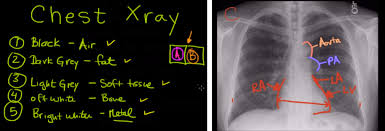

Chest X Ray Interpretation : Interpretation of the chest x ray.. Learn about chest x ray interpretation with free interactive flashcards. Standard frontal chest radiograph (roentgenogram) — upright; Vq mismatch and hyponatremia lectures have been popular. A collection of data interpretation guides to help you learn how to interpret various laboratory and radiology investigations. The chest radiograph remains the most important method of chest imaging, providing an easily accessible, inexpensive, quick, and effective diagnostic tool.

L these two lobes are separated by a major fissure, identical to that seen on the right side, although often slightly more. Dr andrew dixon ◉ and dr jeremy jones ◉ et al. Recognizing normal anatomy on the cxr is key to understanding and interpreting abnormalities. There are many approaches to cxr interpretation, each trying to ensure that key abnormalities are identified and no area is. Vq mismatch and hyponatremia lectures have been popular. Few providers (including mds) are comfortable interpreting their own films. © 2005 adam guttentag, md. Standard frontal chest radiograph (roentgenogram) — upright;

Interpretation of the chest x ray. Chest x ray is probably the most common imaging test. In addition to text and pictures, this tutorial contains interactive features which supplement the text and make it a more dynamic learning. Examination of the chest x ray is a process which requires a systematic approach. Standard frontal chest radiograph (roentgenogram) — upright; Recognizing normal anatomy on the cxr is key to understanding and interpreting abnormalities. Few providers (including mds) are comfortable interpreting their own films. In fact every radiologst should be an expert in chest film reading. Normal heart size is half of the chest width. Generally speaking, a normal cxr should have the lungs looking like zebras in that they are all black with strips. The aim of this study was to investigate the diagnostic accuracy of cxr interpretation by reporting radiographers (technologists). The chest radiograph remains the most important method of chest imaging, providing an easily accessible, inexpensive, quick, and effective diagnostic tool. Learn about chest x ray interpretation with free interactive flashcards.